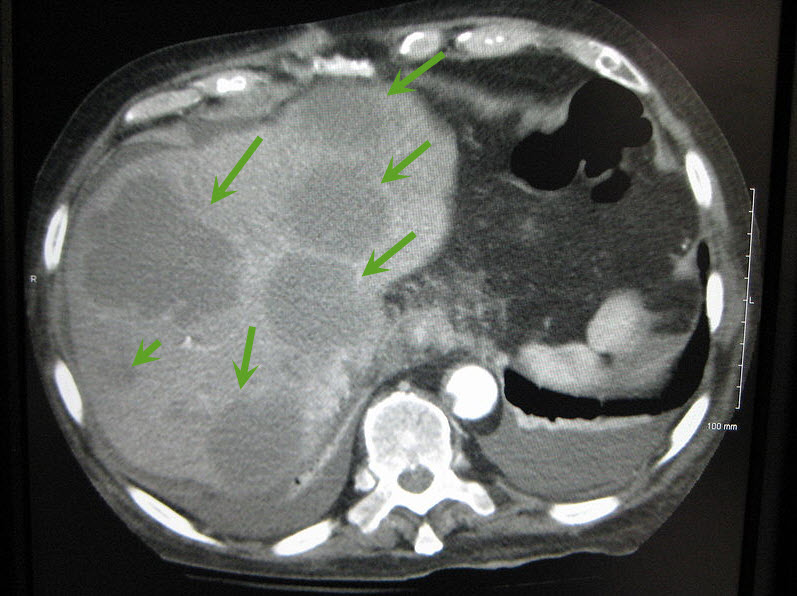

| Axial CT of the abdomen showing multiple liver metastases. Image courtesy of James Heilman, MD / Wikimedia Commons / CC-BY-SA-3.0 |

The majority of liver metastases present as multiple tumors. Only 10% of all cases present with a solitary metastatic lesion. Moreover, in more than three-quarters (3/4) of patients with liver metastases, there is involvement of both lobes of the liver.